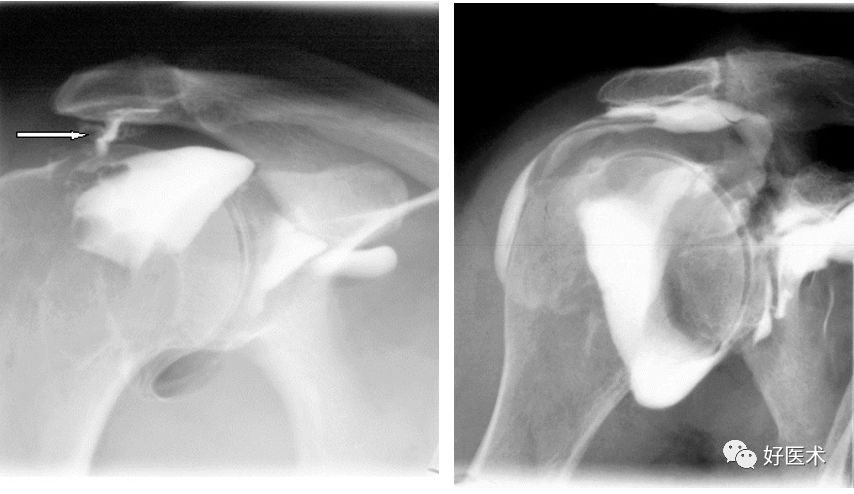

肩关节造影

CT关节造影

CT肩关节造影